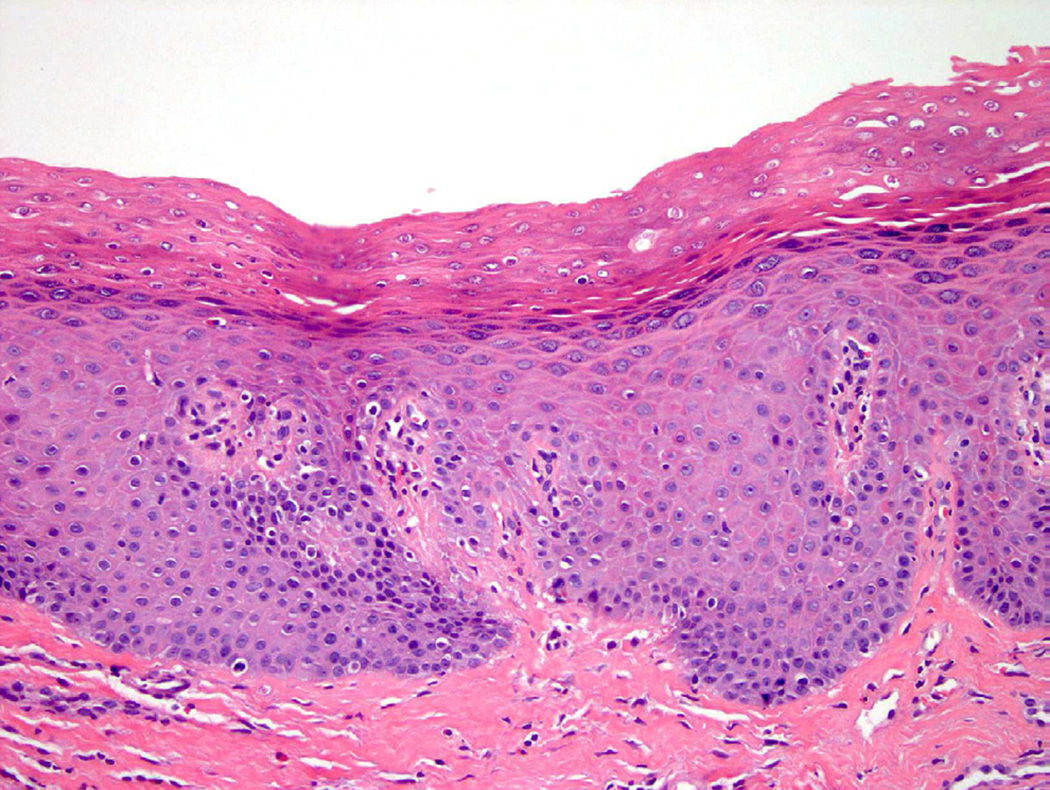

Squamous metaplasia

Squamous metaplasia of the bladder involves replacement of urothelium by squamous epithelium and may be either non-keratinizing or keratinizing. In some instances, non-keratinizing squamous metaplasia is normal, such as in the trigone of the bladder in women21. Chronic inflammatory processes, often seen in patients with spinal cord injury or persistent in-dwelling catheters, may increase the likelihood of developing squamous metaplasia, which can present as leukoplakia on cystoscopy. Although keratinizing squamous metaplasia is traditionally associated with cystitis, bladder stones, and schistosomiasis, it may also be associated with concurrent or subsequent malignancy and thus should be regarded with higher suspicion and additional clinical followup (Fig. 10)22.

Figure 10.

Keratinizing squamous metaplasia.